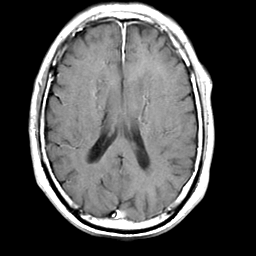

Meningioma, MR Study #2 -- Slice #12

[Home][Help][Clinical] Slice 12